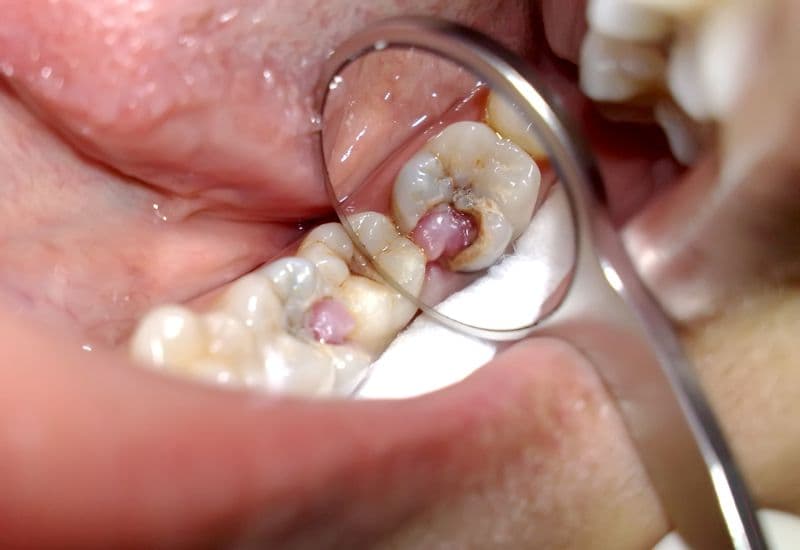

Viêm tủy răng không hồi phục là giai đoạn viêm nặng, khi mô tủy bị tổn thương sâu đến mức không thể tự lành.

2.1. Đặc điểm của viêm tủy răng không hồi phục là gì?

Theo Cleveland Clinic, các dấu hiệu thường gặp gồm:

- Có cảm giác đau khi được bác sĩ gõ hoặc kiểm tra lực tác động nhẹ.

- Nhạy cảm với đồ nóng, lạnh hoặc đồ ngọt, có thể là cảm giác đau nhói, đau âm ỉ hoặc đau thành từng cơn. Đây là triệu chứng tiêu biểu giúp phân biệt với viêm tủy có hồi phục (chỉ ê buốt thoáng qua).

Trong trường hợp tủy đã hoại tử, người bệnh có thể không còn cảm giác với nóng – lạnh – đồ ngọt, nhưng răng vẫn đau khi bị gõ. Điều này xảy ra vì mô tủy chết không còn phản ứng, trong khi vùng quanh răng đang viêm nặng.

Ở giai đoạn này, mô tủy bị tổn thương nghiêm trọng và không còn khả năng tự chữa lành. Việc trì hoãn điều trị có thể dẫn tới nhiễm trùng lan rộng, gây biến chứng nguy hiểm như áp xe hoặc viêm mô tế bào.